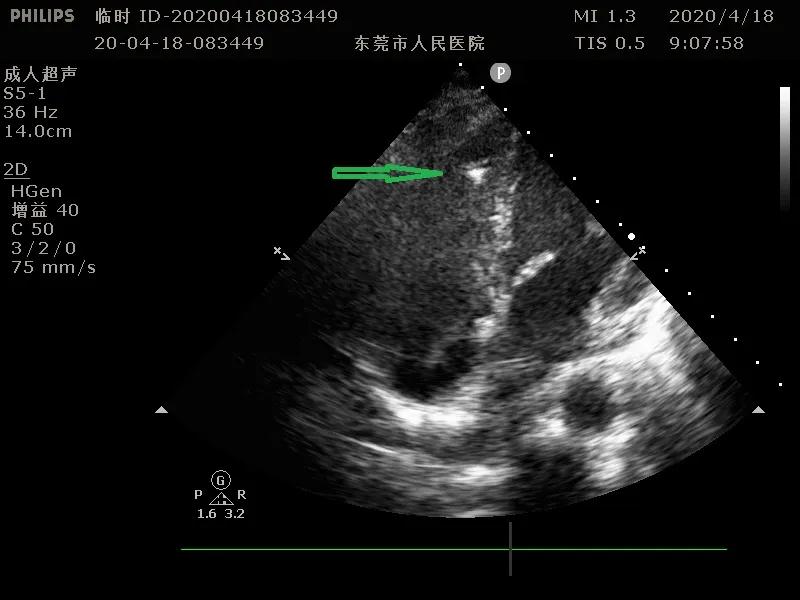

术中超声引导下放置起搏电极

在超声引导下,电极经上腔静脉后顺利进入右心房,跨越三尖瓣,顺利到达右室心尖部,经过起搏测试,起搏参数良好,但起搏时QRS波形明显增宽,考虑高心尖部起搏比例可能导致心功能下降,手术团队追求精益求精,多次调整起搏器电极位置,最终将起搏电极固定于低位间隔,起搏图形良好、参数良好。

术者通过彩超观察电极导线的位置

电极导线到位后通过彩超判断电极预留长度及三尖瓣反流情况,再进行缝合固定,最后连接上仅有7.5CC的小体积,长寿命的心系列起搏器后,起搏器随即进行起搏,将患者心率恢复到正常60次/分,手术顺利完成。术后患者症状明显改善,胎儿情况正常,目前已顺利出院。